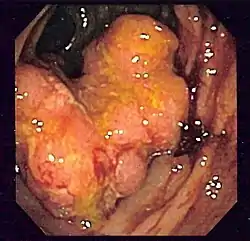

Coloscopie

Tumeur du côlon sigmoïde (observé par endoscopie lors d'un dépistage de maladie de Crohn).

La coloscopie est l'examen de référence : une sonde (long flexible enrobé de plastique) est insérée par l'anus puis glissée peu à peu dans l'intestin (sous anesthésie générale en général). Il permet d'observer la muqueuse de l'anus jusqu'à la jonction iléo-colique, au niveau du cæcum et de l'appendice iléo-cæcal, et de faire des prélèvements. Si un polype est découvert, il est enlevé entièrement et sera analysé au laboratoire par histologie ; son exérèse diminue beaucoup le risque de cancer (voir ci-dessous le paragraphe Prévention). La sigmoïdoscopie est un examen plus rapide, mais moins complet, fait au moyen d'une courte sonde semi-rigide qui permet l'exploration du rectum et du côlon sigmoïde, mais pas du reste du côlon.